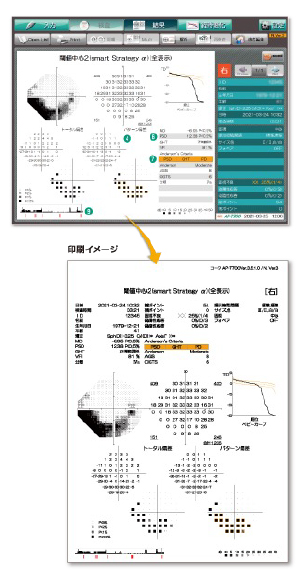

コーワ AP-7700

自動静的視野計

主な特徴

・smart Strategyという視野予測モデルを利用することにより検査中の応答状況から効率よく指標呈示を行うことで正確性(再現性)を確保した検査時間短縮を実現しています。

・smart Strategyαは高精度視野予測に加えて、短時間プログラム(クイック1)を合わせることによってさらなる検査時間短縮をしています。

・動的視野検査も実施でき周辺視野と中心視野の同時評価が可能です。

・視野障害等級判定がすぐにできます。

医師が時系列で症状を分析することにより治療方針が立てやすく、患者様にも診察においてひとめで症状が伝わりやすいです。

視覚障害等級の判定が当院でも素早く即日で行うことができます。